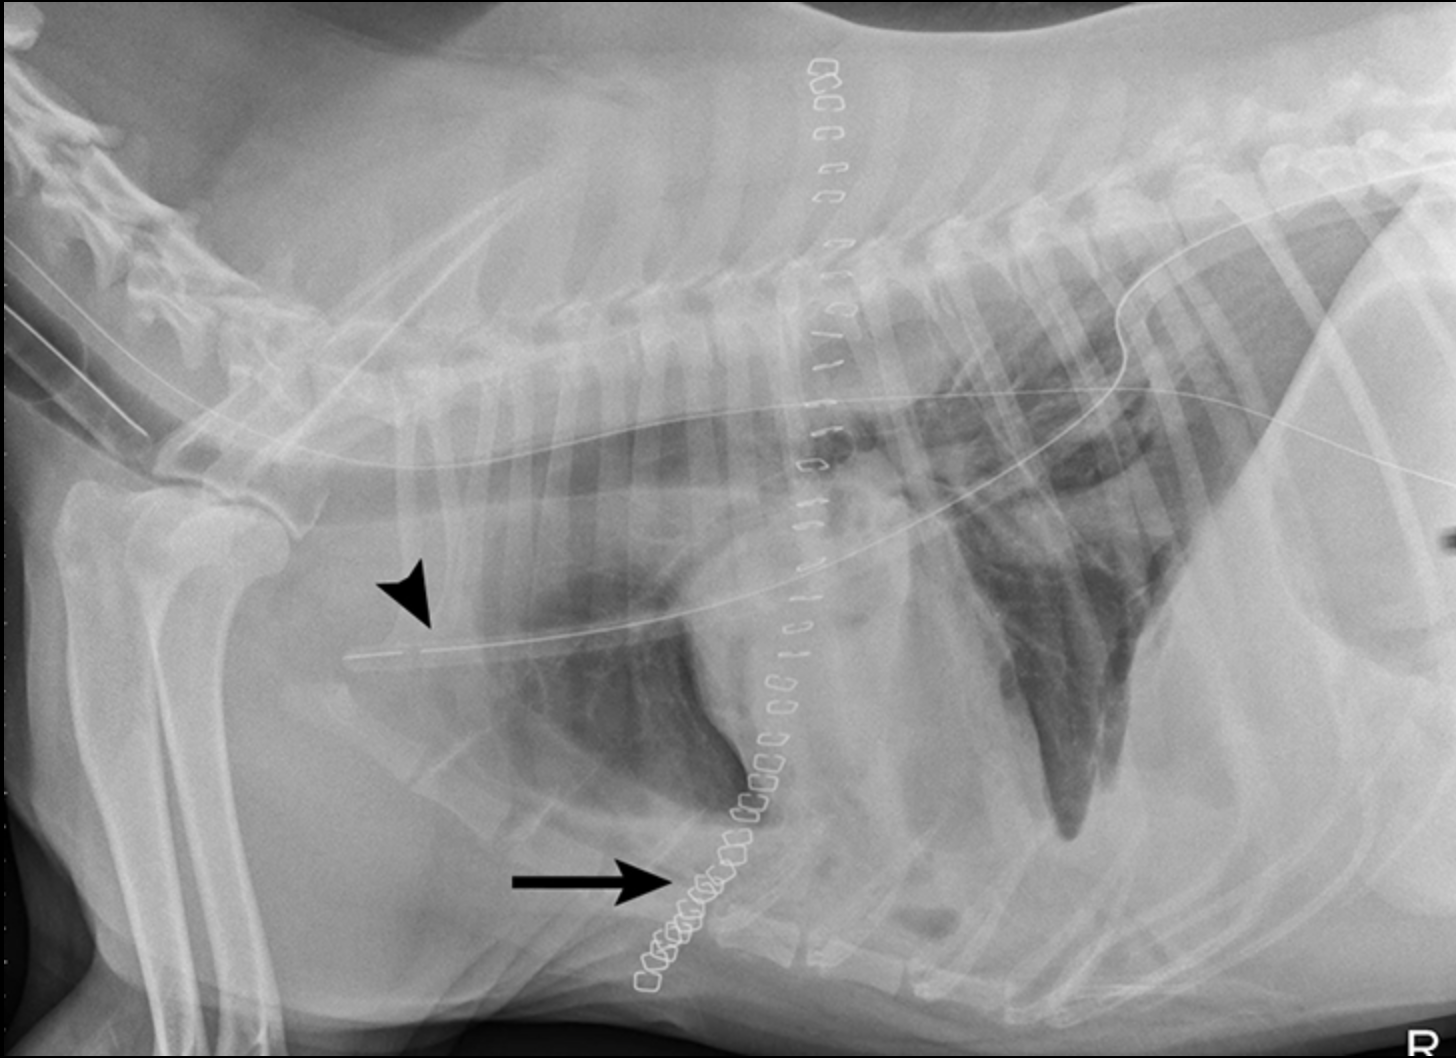

Las radiografías obtenidas después de la toracocentesis demostraron un derrame pleural mejorado y la consolidación del lóbulo medio izquierdo del pulmón (Figura 3). Basado en el abultamiento de los tejidos blandos cerca del hilio y el broncoramón de aire que se extiende cranealmente, el diferencial primario fue la torsión del lóbulo pulmonar (LLT). Otras consideraciones incluyen masa pulmonar, absceso o granuloma.